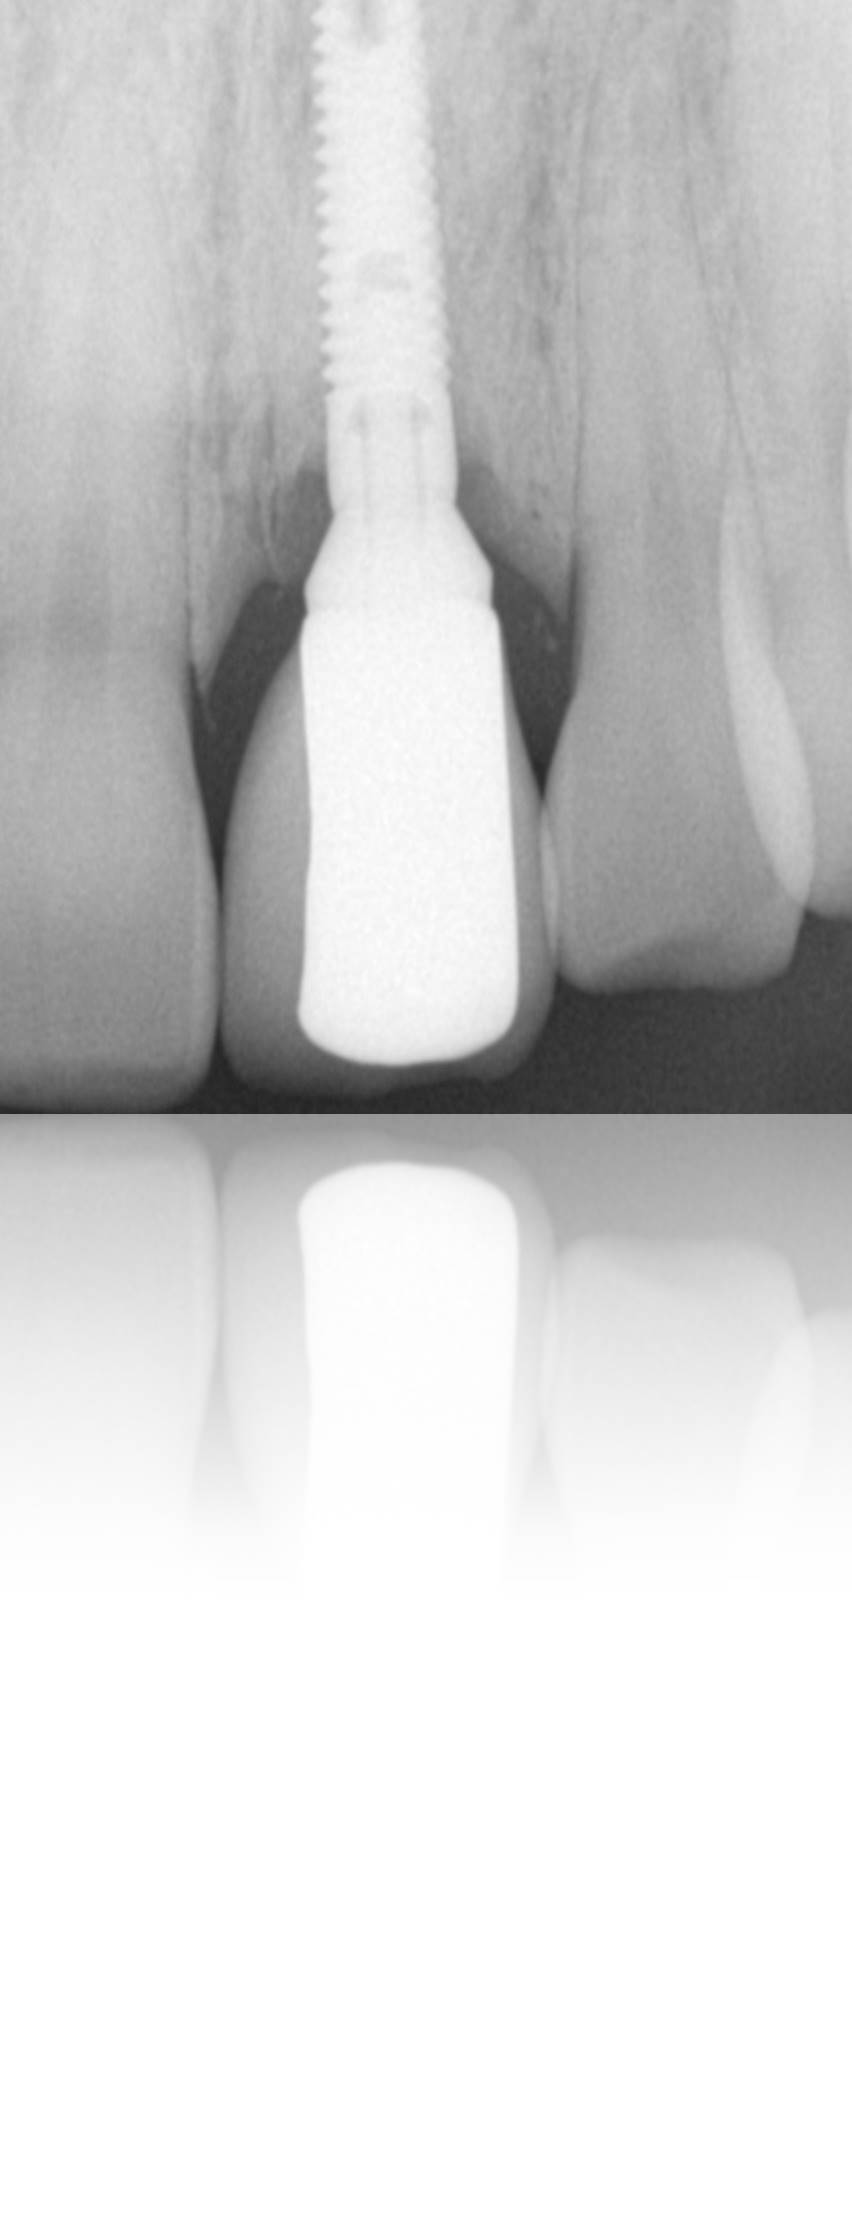

Figure 27. The access holes were sealed with composite, masking any evidence of the underlying metal abutment and/or implant screw.

Figure 27

Figure 28. Radiograph taken 4 years after placement demonstrating stable and healthy peri-implant bone and no indication of peri-implant disease.

Figure 28